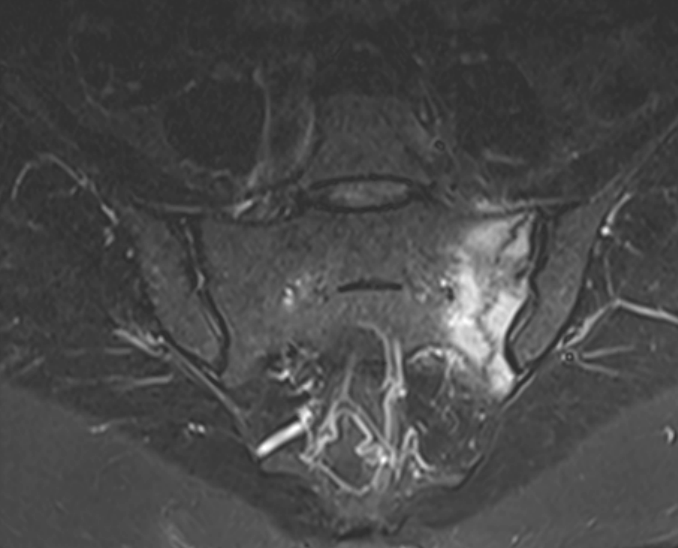

3. Left sacral insufficiency fracture